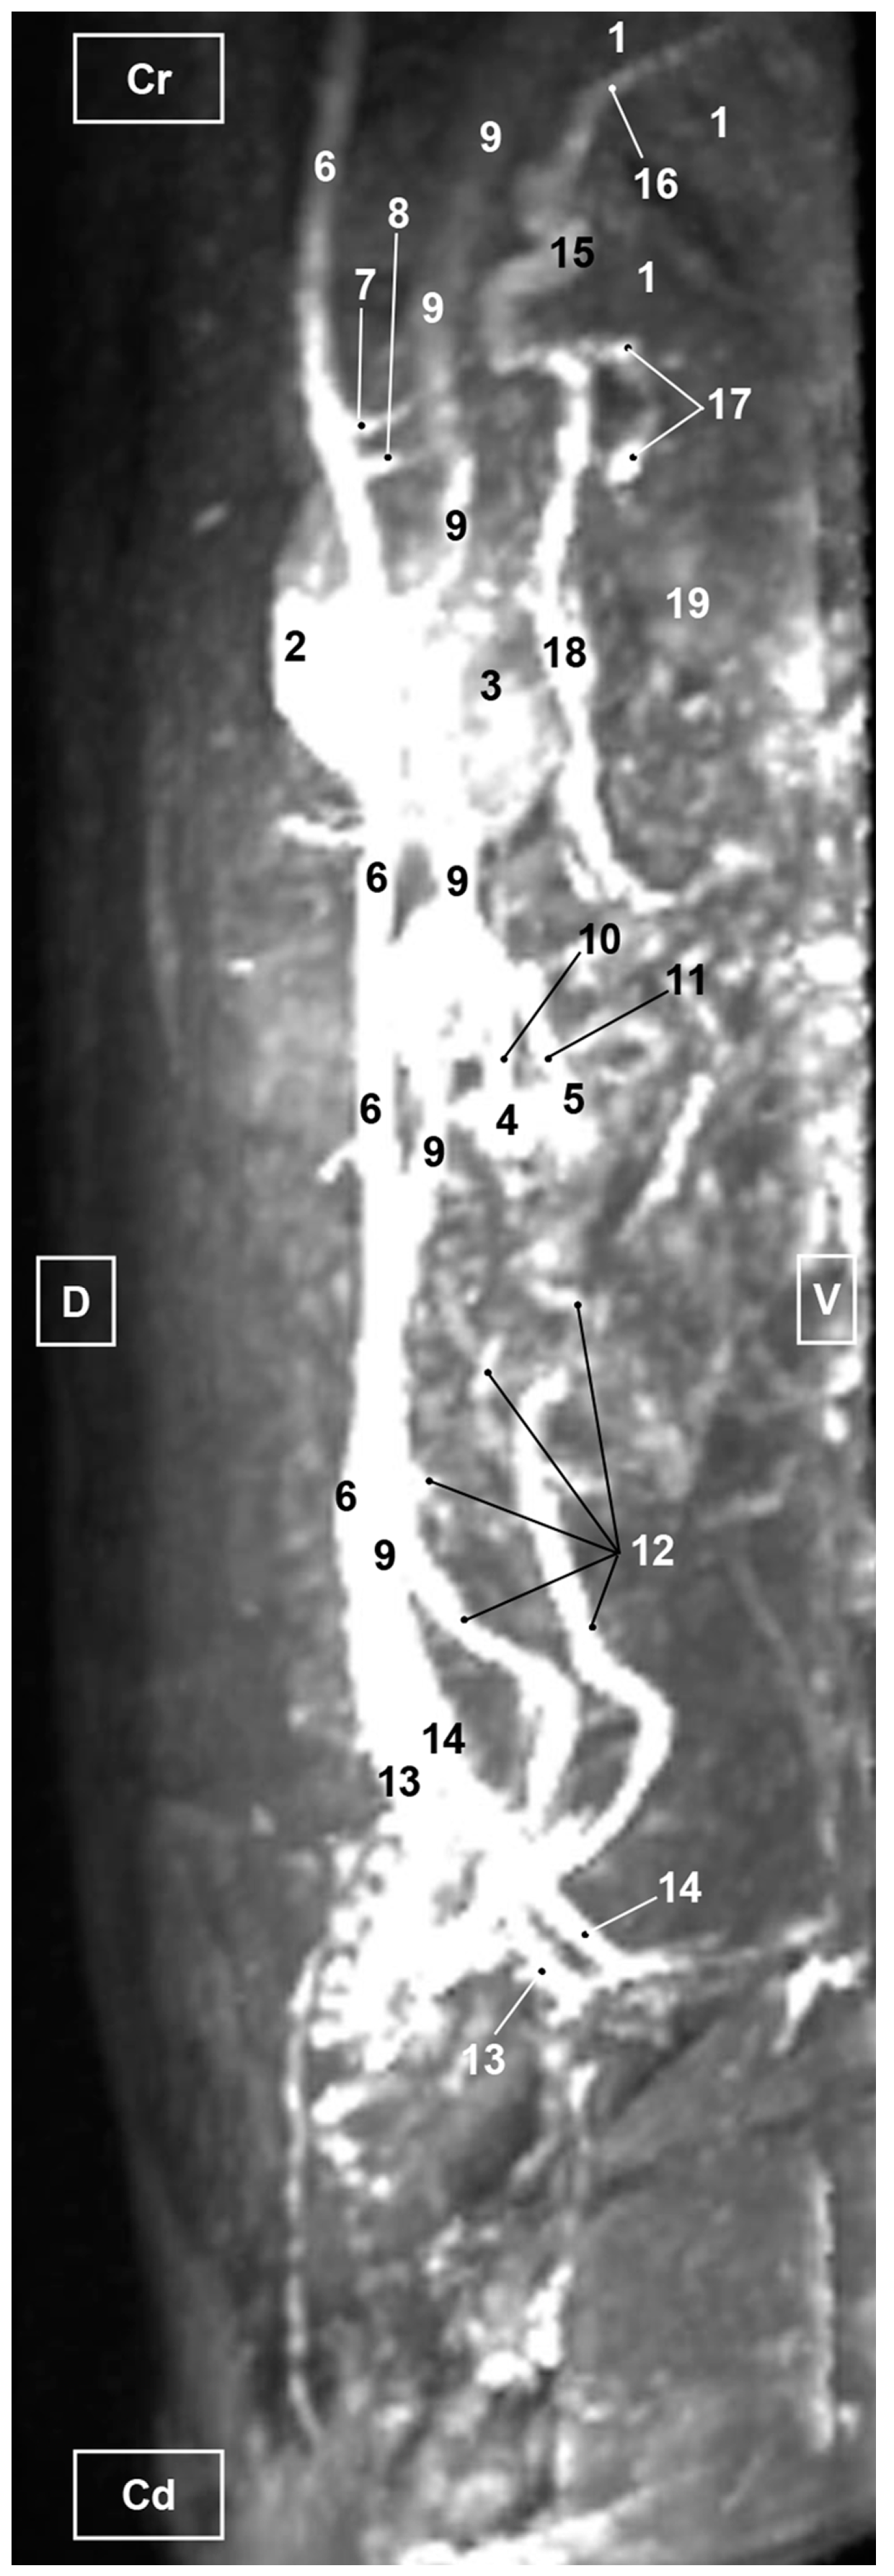

3.3. Magnetic Resonance Angiography

3.3.1. Arterial System

3.3.2. Venous System